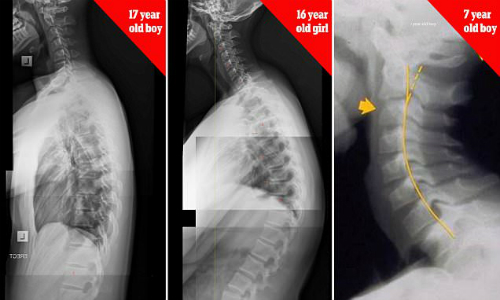

Yêu công nghệ là 1 việc tốt vì sẽ khiến con người luôn cố gắng tìm tòi và học hỏi, thế nhưng nếu quá nghiện sẽ trở thành tai họa. Nếu trẻ em nghiện smartphone từ sớm và cả giới tuổi vị thành niên thì nguy cơ bị gù là rất cao do phải cúi đầu xuống chiếc điện thoải hàng giờ liền, điều này ảnh hưởng tới sự phát triển xương sống của trẻ.

Nhiều phụ huynh khi thấy con em dùng điện thoại chỉ quan tâm liệu trẻ có xem các nội dung không phù hợp mà không nhắc nhở về tư thế ngồi. Chuyên gia trị liệu cột sống là tiến sĩ James Carter (Australia) cảnh báo trẻ em 7 tuổi có thể bị gù lưng, cong vẹo cột sống do sử dụng smartphone và tablet quá nhiều. Hội chứng được gọi là "chiếc cổ nhắn tin" đang gia tăng một cách đáng báo động.

Theo Telegraph, tiến sĩ Carter thường xuyên tiếp những bệnh nhân phàn nàn bị đau đầu mà nguyên nhân do những thiết bị điện tử. "Cách đây 2 năm, tôi đã nhận thấy có quá nhiều trường hợp như vậy, đặc biệt trẻ em và thiếu niên chiếm đến 50% số bệnh nhân", tiến sĩ cho hay. "Hiện tượng này được gọi là 'chiếc cổ nhắn tin' bởi nó xảy ra khi con người ngồi cúi đầu, dán mắt vào điện thoại liên tục hàng giờ. Từ đó dẫn đến thoái hóa đốt sống cổ; đau đầu, cổ, vai và lưng". Ngoài tổn thương cột sống, nghiện smartphone còn dẫn đến lo âu và trầm cảm.

Sammy Margo từ Hiệp hội Vật lý trị liệu Anh đồng ý với nhận định càng ngày càng có nhiều người bị tình trạng "chiếc cổ nhắn tin". "Khi cúi đầu quá lâu, bạn sẽ thay đổi toàn bộ cấu trúc xương. Kết hợp với lối sống ít vận động, điều này sẽ gây ra những hậu quả nghiêm trọng", bà nói.